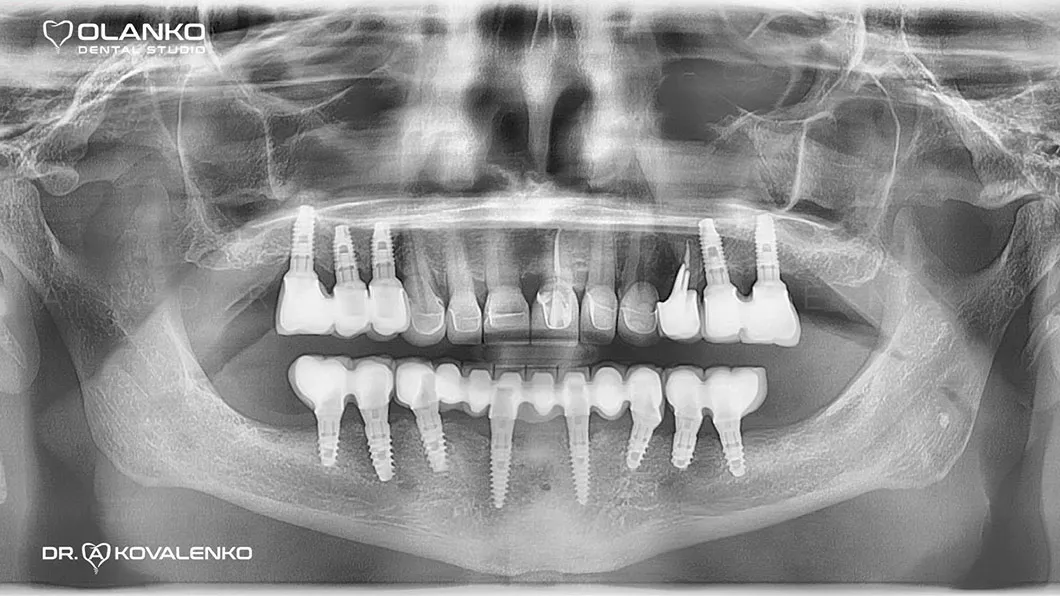

Пациент обратился с жалобами на нарушение функции жевания и эстетики, в связи с отсутствием зубов, а также значительной подвижности зубов на нижней челюсти.

Удаление зубов на верхней и нижней челюсти с одномоментной установкой зубных имплантатов по шаблону. Костная пластика.

Клинический случай 1 имплантация зубов